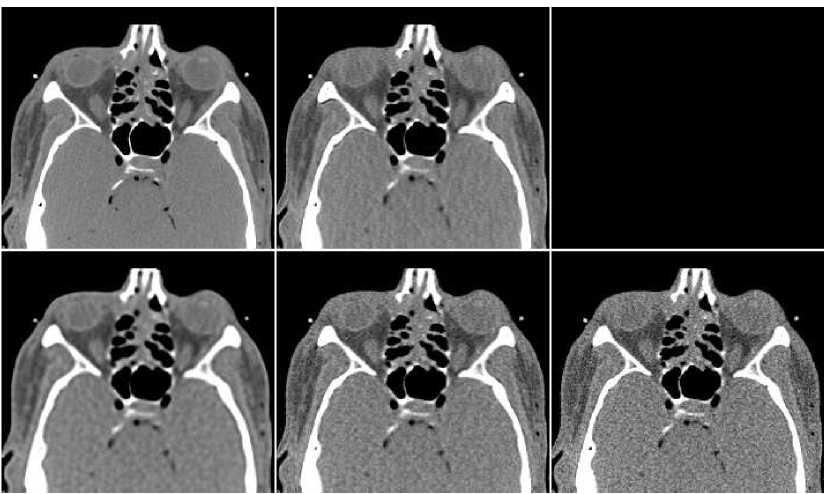

We conducted numerical experiments to demonstrate the proposed method using the same setup as in the FBP experiment. Training data for the ANN was obtained using a data-set of axial male thighs section images. For each, an initial image is computed with the FBP algorithm using a sinogram filter with cut-off frequency value of (see Figure 5). The PWLS algorithm is implemented as described in Section II-B, with parameters , . We have performed iterations, saving an image version every iterations - overall we have a sequence of images. In practice, we use three images out of this sequence, namely those from iterations 20, 60 and 80. From the first and the third images, neighborhoods of radius ( pixels) were taken for the estimation of the pixel value, and the second image contributed a neighborhood of radius ( pixels). Overall, the ANN has inputs. It is set to be a network with neurons in the (single) hidden layer. It has a single output, set to produce only the central pixel of the provided neighborhood. These specific settings were obtained with a manual tuning of the design parameters.

In Figure 10 we display the fusion result along with individual PWLS reconstructions, used in the fusion process. The lower part of the figure contains the absolute-valued error images. The fusion result has a higher visual quality than any of the three underlying images. Comparing to those images, the noise level in the fusion image is the lowest, and the tissue texture is closer to the original. The sharpness is the same as in the lower middle PWLS image. The SNR values (stated in the Figure) also point to the improvement in quality. The SSIM of the fusion image is , while the sequence of PWLS results have the SSIM values of (corresponding to the lower row of Figure 10, left to right). A reconstruction of an additional test image is displayed in Figure 11. The effect of the fusion observed here is similar to the one in the previous reconstruction. We conclude that the ANN-based fusion can contribute also to the iterative reconstruction, without requiring any additional iterations; the computational cost of the fusion, exercised after the reconstruction, is lower by an order of magnitude than that of the iterative process.

In order to test the robustness of the training results, we apply the ANN trained with the thigh sections, for a reconstruction of images of other body parts – sections of the head and the abdomen. Reconstruction results are presented in Figure 13 in the same order as in the previous comparison: middle image in the upper row is the result of fusion, which components are presented in the lower row. The head reconstruction is improved substantially by the fusion process, as visual observation shows. However, the SNR values (given in Table II) point to the favor of the PWLS image corresponding to iterations (lower middle image). The highest SSIM value does belong to the fusion result, though. In the case of the abdomen section, the fusion image is similar to the -iterations version but contains less noise; its quantitative measures are somewhat better than those of the individual PWLS images.